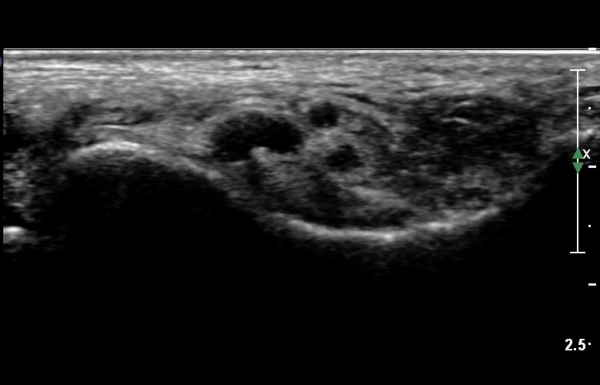

ŽÃËÀÚ¸¦ Á¶±Ý ¸»´ÜÀ¸·Î À̵¿ÇÏ´Ï Èİæ°ñ½Å°æÀÌ ³»ÃøÁ·Àú½Å°æ°ú ¿ÜÃøÁ·Àú½Å°æÀ¸·Î ºÐÁöÇÑ´Ù(»çÁø 2).